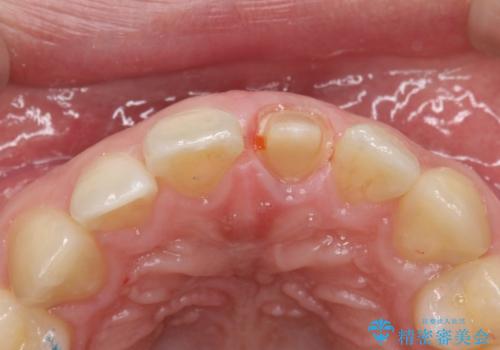

- 前歯の変色を主訴に来院されました。

根管治療は希望されなかったので、リスクを説明した上でオールセラミッククラウンの治療を行っています。

金属の被せ物は歯肉の変色を起こしやすくなります。オールセラミッククラウンは金属を使わないため審美的な治療を行うことができます。